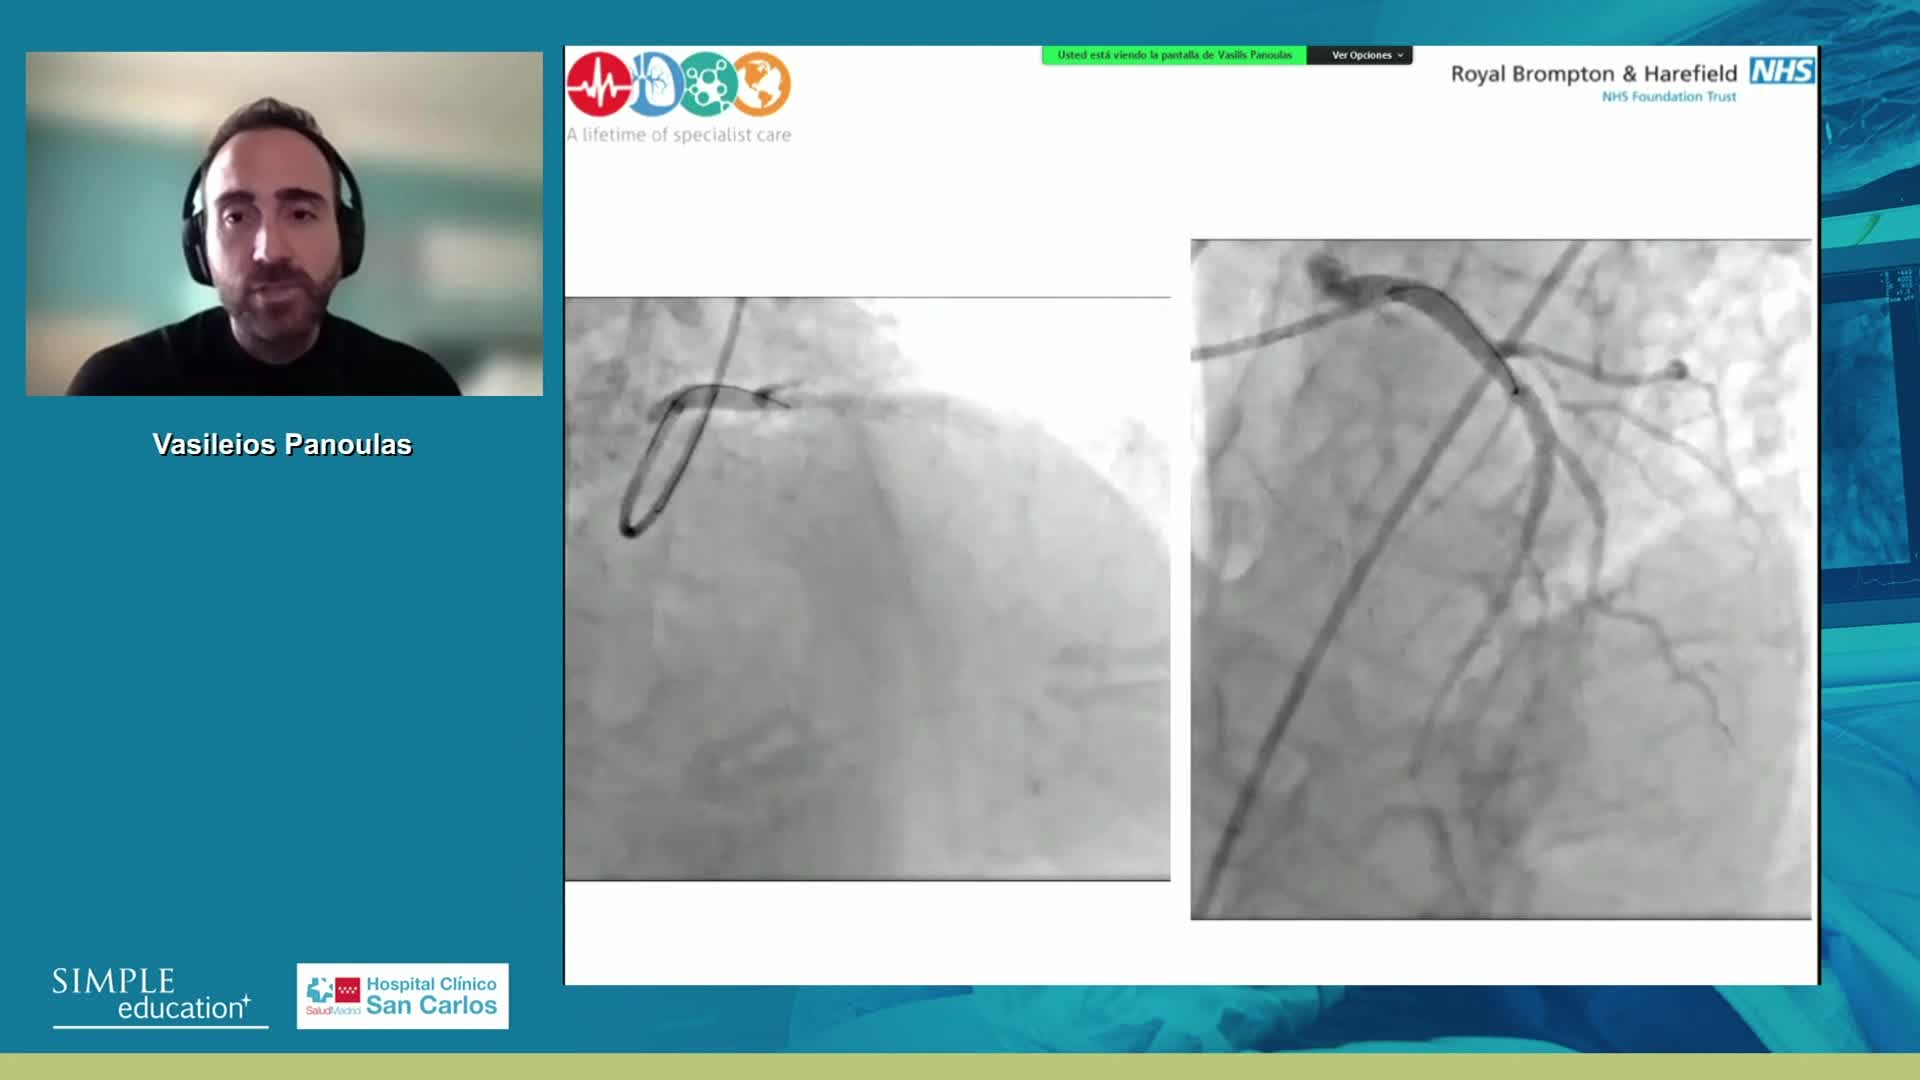

Intracoronary guidance in acute coronary syndromes - Dr Hernan Mejia-Renteria

Coronary Bifurcations: An Update on Diagnosis, PCI planning and Imaging and PhysiologyGuidance - Dr Dejan Milasinovic